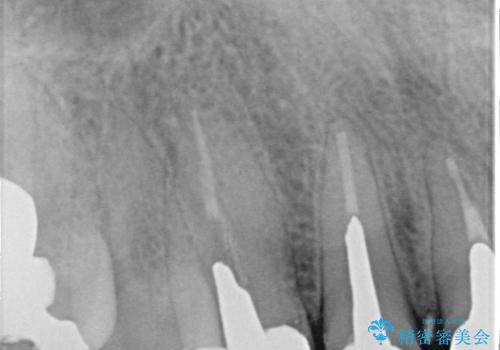

- 以前治療した上の前歯の不自然な保険のかぶせ物を自然なものにしたいとのことで来院されました。

右上の前から1番目から3番目までの歯のかぶせ物を土台から再治療することとなりました。

金属の土台を、ファイバーコアという歯根にやさしく白いものに交換して、かぶせ物をオールセラミックにしました。